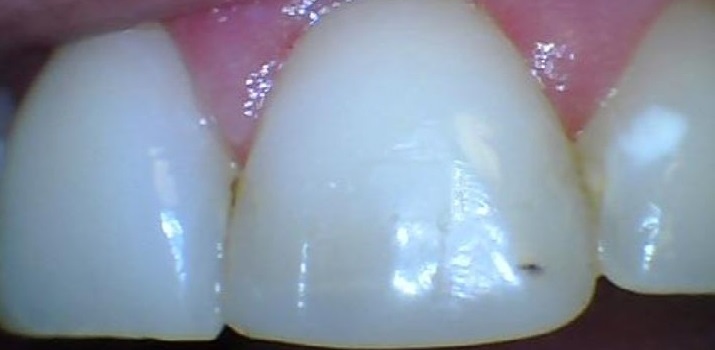

Digital Dental X-Rays

We use the advanced Nomad Pro 2, a handheld X-Ray Unit by Kavo, which is a leading brand in dental technology!

Images are crisp clean, the patient does not experience the gag feeling like the traditional X-Rays do